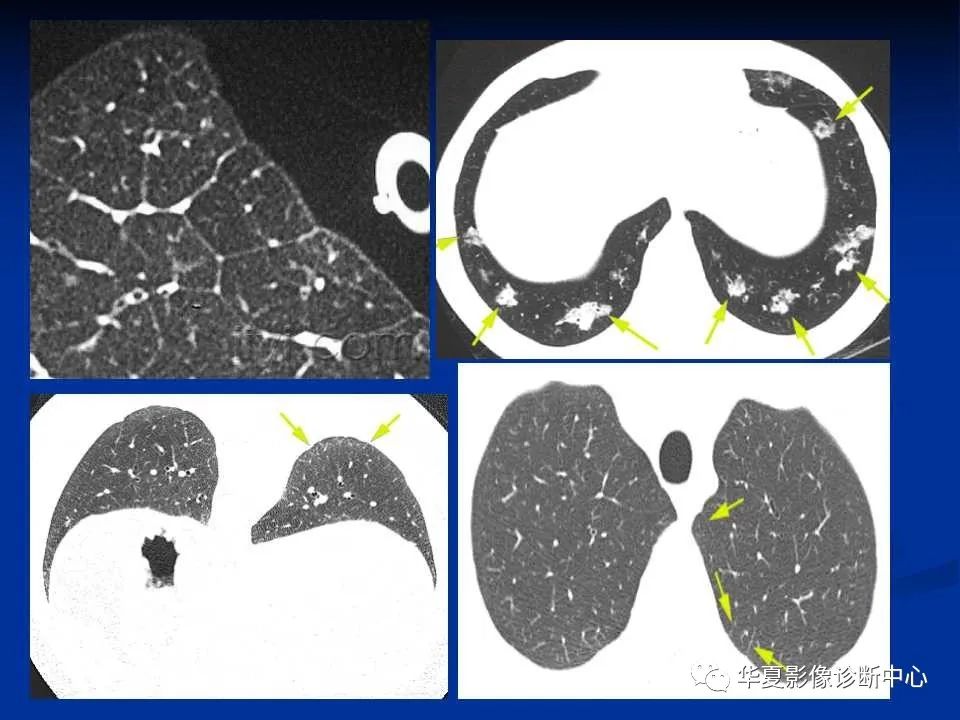

随着全球疫情的演变,COVID-19非冠肺炎的最新动态牵动着每个人的心弦,在这场严峻的战斗中,我们见证了无数英勇的身影,感受到了生命的脆弱与坚韧,也体验到了科技进步带来的希望与挑战,本文将带您深入了解非冠肺炎的最新进展,共同探寻战胜疫情的道路。